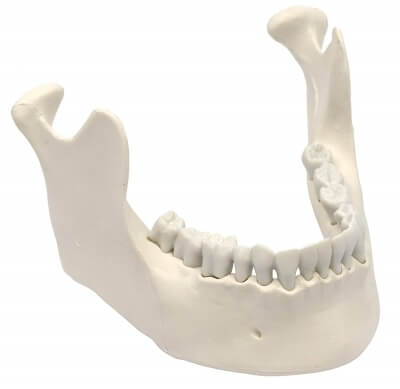

Возрастные аспекты развития костной ткани челюстно-лицевой области и альвеолярного отростка: значение для практической стоматологии

Остеоинтеграция имплантата в костную ткань при эндопротезировании тазобедренного сустава: стадии, механизмы, нарушения и факторы риска